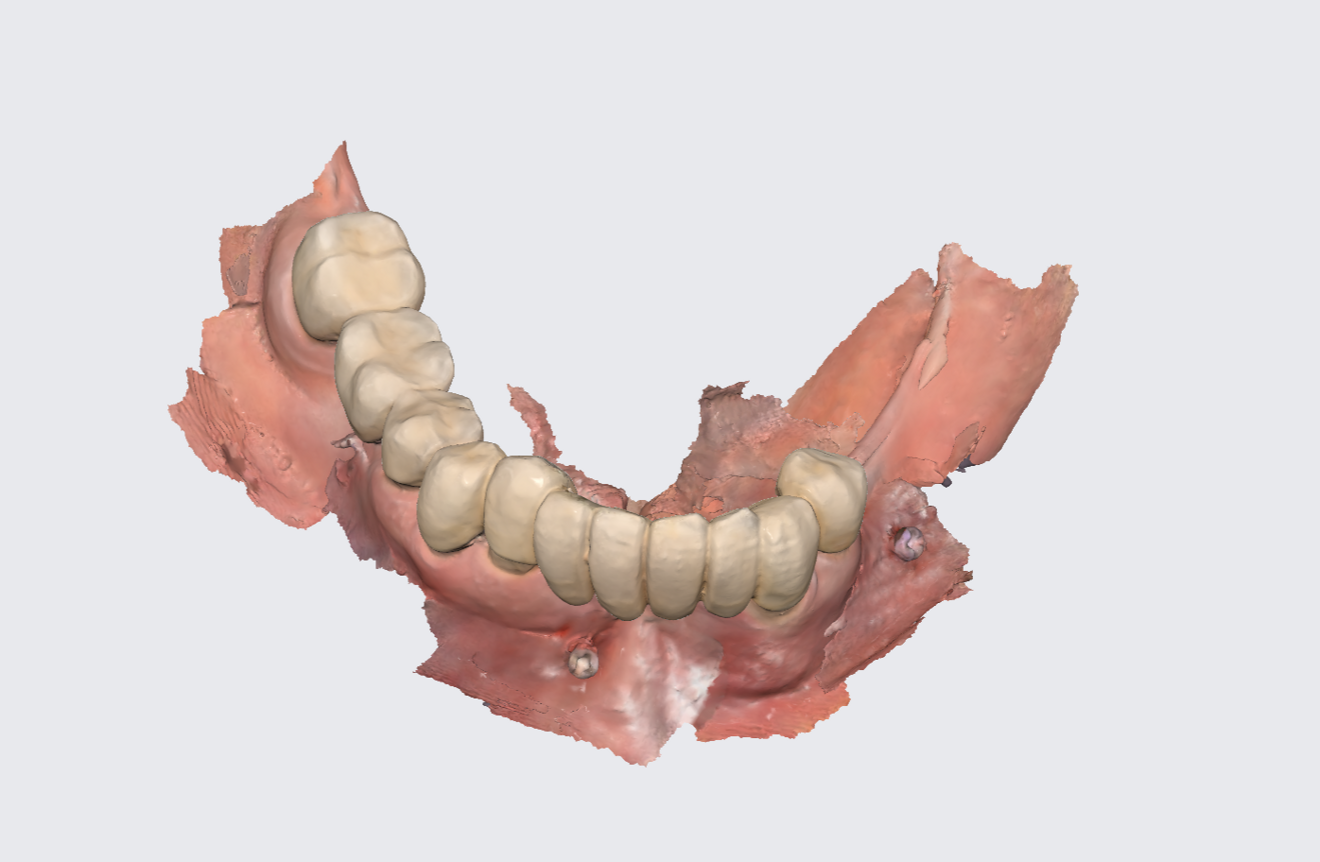

Fig. 1a: Pre-op panoramic radiograph. (All images: Dr Ádám Kapai, Dr Tamás Chikány, Tamás Csornai)

Intra-oral examination revealed compromised mandibular dentition, an old fixed prothesis, missing posterior teeth on the left side, periodontal involvement and gingival inflammation. A panoramic radiograph was obtained, and the findings were reported to the patient (Figs. 1a & b; 2a & b). Both mandibular canines had visible periapical radiolucencies. A CBCT scan was performed for a more detailed assessment of the alveolar bone anatomy (Figs. 3a & b). Temporomandibular joint examination revealed no indication of dysfunction (crepitus, clicking or pain).